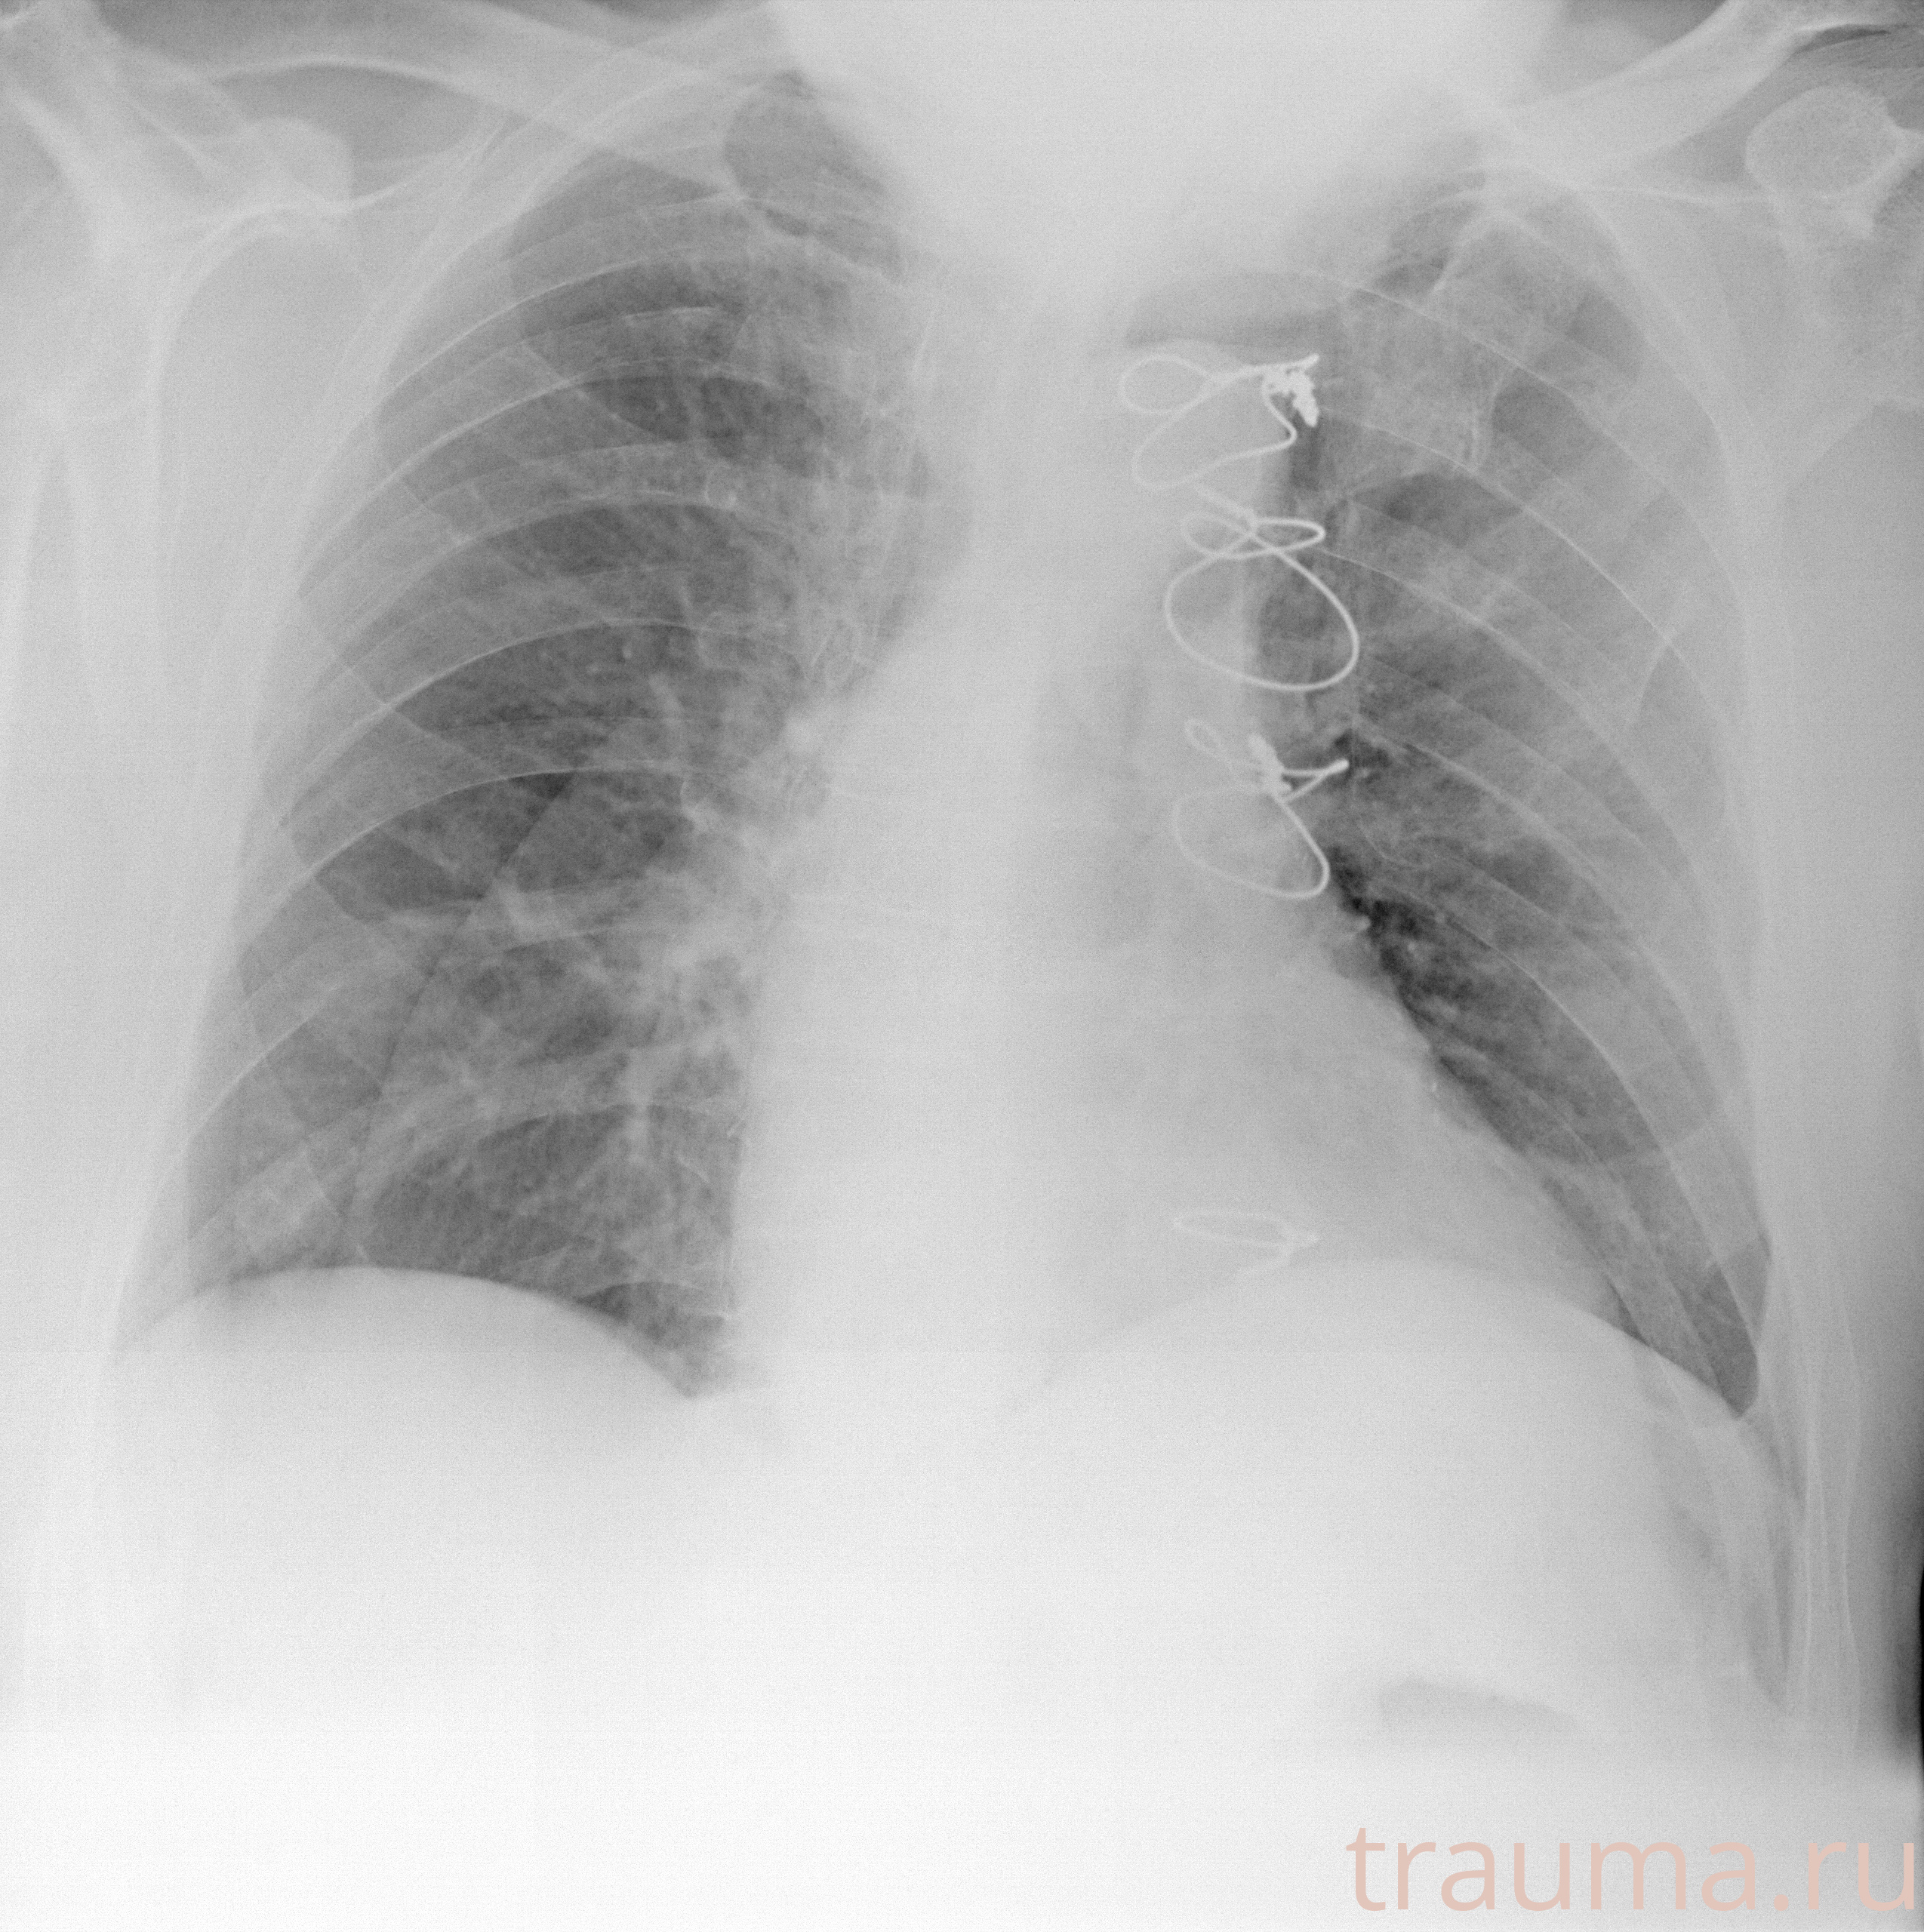

Рентген на дому: по вашему адресу приезжает врач-рентгенолог, травматолог-ортопед с мобильным рентгеновским аппаратом, проводит диагностику травмы или заболевания, делает необходимые рентгенограммы, дает рекомендации по дальнейшему лечению. Получить качественные снимки в домашних условиях возможно благодаря уникальной методике, разработанной МосРентген Центром для института  Склифосовского

при переломе шейки бедра и пневмонии от компании МосРентген Центр - партнера Института имени Склифосовского